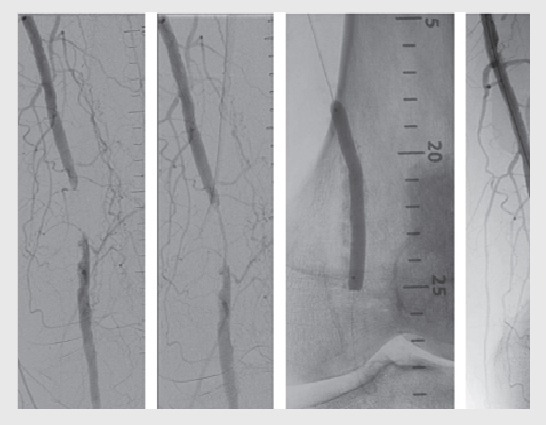

Peripheral coronary Interventions for blockage in the leg arteries

- Angioplasty and stenting: In some cases, minimally invasive procedures like angioplasty (using a balloon to widen the artery) and stent placement (to keep the artery open) may be performed to improve blood flow.

- Atherectomy: As mentioned earlier, atherectomy may be used to remove plaque from the arteries and improve blood flow in certain cases.